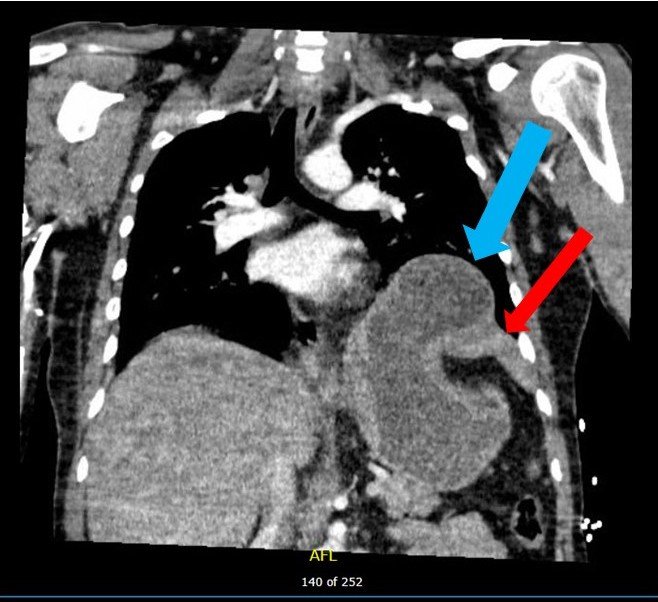

Although uncommon, traumatic diaphragmatic rupture (TDR) from blunt force injury is difficult to diagnose and can lead to serious complications if left untreated. Associated symptoms are often non-specific, which can make detection of the injury difficult. Here we present a case report of a patient who suffered a left-sided TDR after blunt trauma. Upon arrival at the emergency department, the patient denied pain but had tenderness to palpation over the epigastrium. A chest X-ray showed an elevated diaphragm on the left with mediastinal shift to the right, and a diagnosis of TDR with stomach herniation was confirmed by computed tomography (CT). The patient was admitted to surgery for reduction and repair and later discharged in good condition. This case report highlights the importance of suspecting TDR in high energy injury mechanisms presenting to the emergency department.